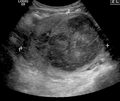

A very large (9 cm) fibroid of the uterus which is causing pelvic congestion syndrome as seen on ultrasound